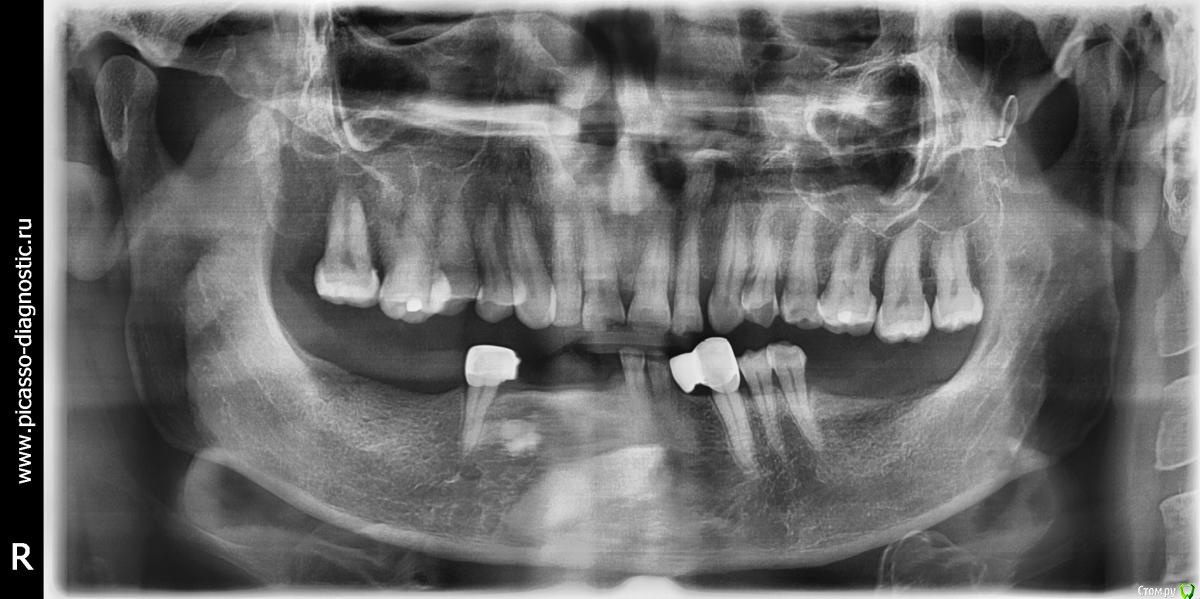

Tatyana_k Опубликовано 19 января, 2019 Поделиться Опубликовано 19 января, 2019 Мужчина 52 года нуждается в ортопедическом лечении. Направила на на ОПТГ. И собственно вопрос, что за уплотнения в кости нижней челюсти? Планируем бюгельный протез на нижнюю челюсть, хотелось бы без сюрпризов. Из анамнеза: 4 года назад пациент попадал в автомобильную аварию, были травмированы нижние зубы ( несколько пришлось удалить), а также перелом челюсти в 2 х местах. Уважаемые коллеги, прошу высказать свое мнение по поводу этих образований. Неизвестность настораживает. С уважением и вниманием к Вам, Татьяна. Ссылка на комментарий

Дмитрий Л. Опубликовано 19 января, 2019 Поделиться Опубликовано 19 января, 2019 То что выше, возможно одонтома, то что ниже - ретенированный клык/премоляр. Делайте Кт. По оптг никогда фронтальный участок не оценивайте. 6 Ссылка на комментарий

Дмитрий М Опубликовано 20 января, 2019 Поделиться Опубликовано 20 января, 2019 То что выше, возможно одонтома, то что ниже - ретенированный клык/премоляр. Делайте Кт. По оптг никогда фронтальный участок не оценивайте.КЛКТ +1 Ссылка на комментарий

Tatyana_k Опубликовано 20 января, 2019 Автор Поделиться Опубликовано 20 января, 2019 КЛКТ +1Спасибо Всем за ответы, весьма признательна. ) Я тоже по первому впечатлению подумала о ретенированном клыке, но есть какая - то неопределенность в этом образовании..., подумала, лучше подстраховаться.) Ссылка на комментарий